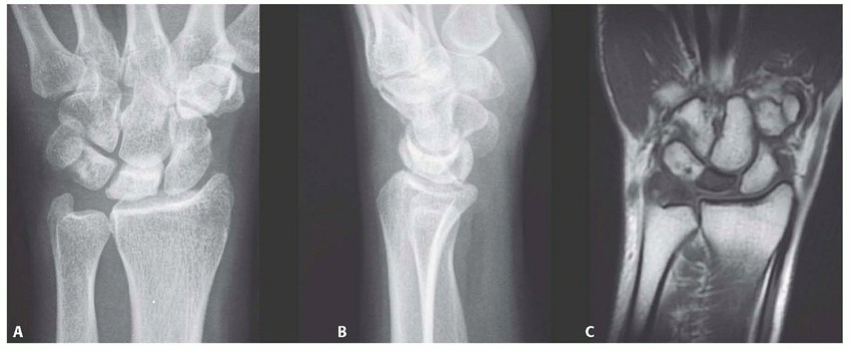

Meticulous preoperative planning is the cornerstone of executing this complex dual-intervention strategy. The surgeon must synthesize clinical findings with advanced imaging modalities to confirm the disease stage, assess the biological viability of the lunate, and precisely template the capitate osteotomy. A standard radiographic series, including high-quality posteroanterior (PA), true lateral, and oblique views of the wrist, is the starting point. These plain films allow for the calculation of ulnar variance, assessment of carpal height (carpal height ratio), and evaluation of the Lichtman stage based on lunate sclerosis and collapse.

While plain radiographs are essential, Magnetic Resonance Imaging (MRI) is the definitive modality for staging Kienböck disease and determining candidacy for a vascularized bone graft. High-resolution MRI without and with intravenous gadolinium contrast is mandatory. T1-weighted coronal images are utilized to assess the extent of marrow replacement and ischemia; a homogeneous loss of the normal high-signal fatty marrow confirms avascular necrosis.

T2-weighted and Short Tau Inversion Recovery (STIR) sequences are critical for identifying occult fracture lines, bone marrow edema, and the presence of cysts within the lunate. Most importantly, high-resolution sagittal and coronal T2-weighted sequences must be rigorously scrutinized to evaluate the integrity of the lunate's articular cartilage envelope.

If the MRI reveals a complete disruption of the dorsal or volar cartilaginous shell, or severe fragmentation of the subchondral plate, the patient is downgraded from a joint-preserving procedure to a salvage operation. Gadolinium-enhanced sequences can occasionally demonstrate residual areas of perfusion within the lunate, which may influence the exact placement of the vascularized graft.

Templating the capitate shortening osteotomy is performed on the preoperative PA radiograph. The goal is to resect a precise 2.0-millimeter wafer of bone from the capitate waist. Resecting less than 1.5 mm may not provide sufficient mechanical offloading, while resecting more than 2.5 mm can lead to excessive laxity of the midcarpal ligaments and subsequent carpal instability. The osteotomy cuts must be planned perpendicular to the long axis of the capitate, ensuring that the proximal and distal fragments will appose flushly without angular deformity once compressed.